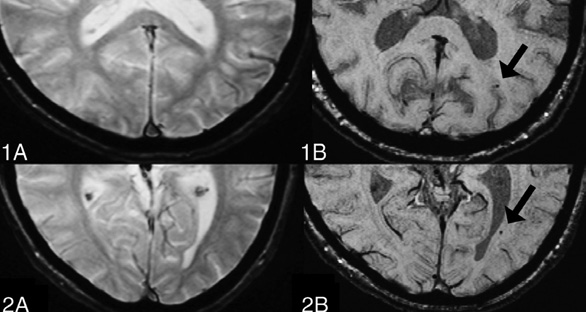

CMBs appear as small (2–10 mm in diameter), round or ovoid hypointense foci which exhibit blooming artifacts, thus making them more conspicuous on MRI sequences that are sensitive to susceptibility effects.

TMBs are detected in 27% of mild, 47% of moderate, and 58% of severe TBI cases. In contrast to microbleeds associated with small vessel disease or other non-traumatic conditions, traumatic CMBs exhibit distinct characteristics in terms of their location and appearance [17]. These trauma-induced lesions are frequently found in the corpus callosum and at the interface between the grey and white matter. Moreover, traumatic CMBs typically display a more radial and linear pattern, often aligning with the perivascular spaces. This configuration differs noticeably from the rounded shape commonly observed in CMBs linked to small vessel disease (SVD) [17]. These differences in distribution and morphology can aid in distinguishing traumatic from non-traumatic microbleeds in neuroimaging. However, absolute differentiation between these lesions remains challenging.

SWI has several limitations, including its reliance on phase images that may fail to accurately depict local anatomical structures and its sensitivity to the orientation of objects relative to the magnetic field. Interpreting complex regions, such as the basal ganglia, is particularly challenging with SWI due to these constraints. To address these limitations, Quantitative Susceptibility Mapping (QSM) has been proposed as a superior alternative, offering notable advantages, especially in detecting microbleeds in mild traumatic brain injury (mTBI) [21]. Unlike SWI, QSM provides a more precise and quantitative assessment by directly measuring tissue susceptibilities, which improves the accuracy in evaluating the size and concentration of microbleeds. Additionally, QSM minimizes the common SWI artifacts, such as blooming effects, resulting in clearer and more reliable imaging, particularly in complex anatomical regions where SWI may struggle. QSM also enhances contrast sensitivity, allowing for the detection of smaller or more subtle microbleeds that might be missed with SWI. Furthermore, QSM has the ability to differentiate between microbleeds and other brain deposits, like calcifications, ensuring a more accurate diagnosis and effective monitoring of brain injuries [21]. Overall, QSM offers a more advanced and effective approach for the assessment and characterization of microbleeds, supporting improved clinical outcomes and more precise treatment planning.